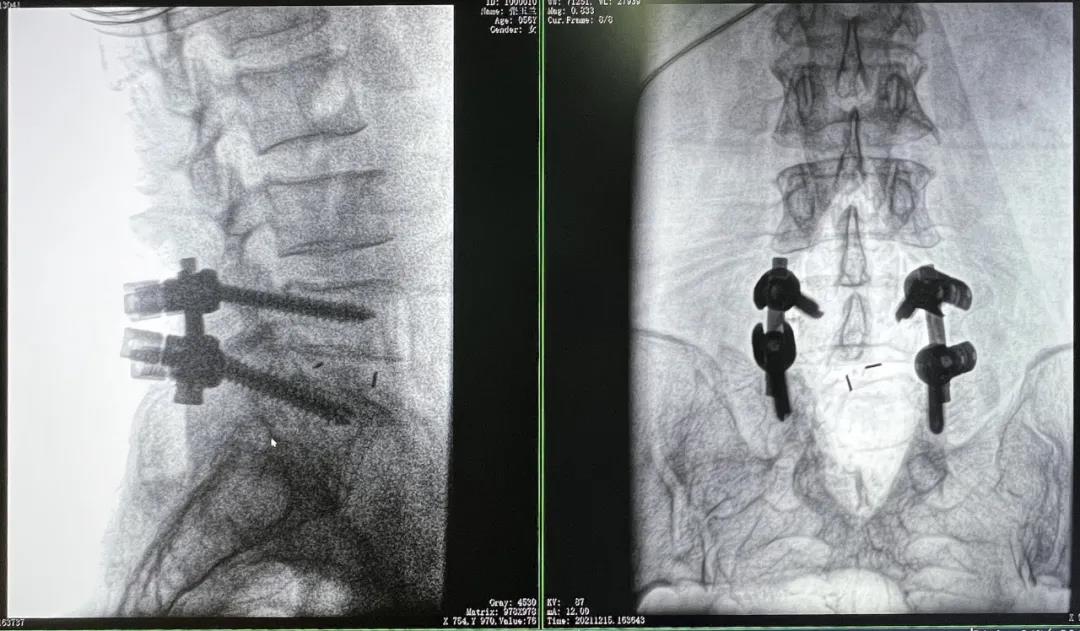

3D C形臂擺位及手術前二維影像

醫生在影像引導下在L5/S1椎弓根處打入醫用螺釘

術中快速生成橫斷面、矢狀面、冠狀面斷層圖像和三維立體圖像